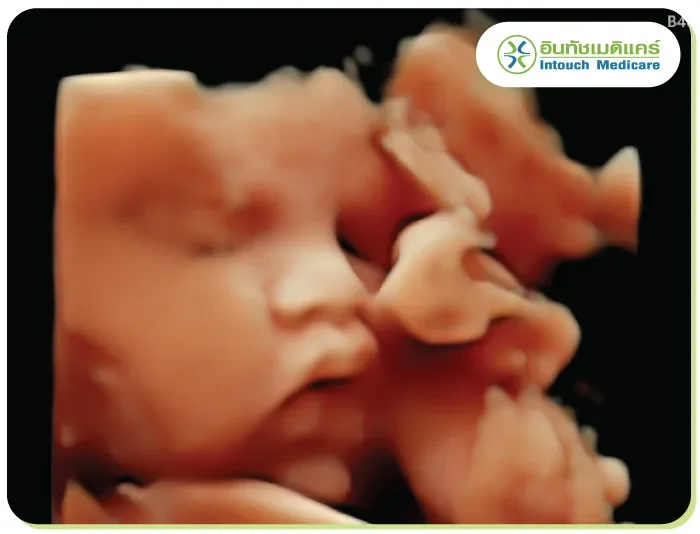

This type provides images with width, height, and depth by capturing reflected sound waves and processing them through computer software. The resulting images are more detailed and lifelike compared to 2D ultrasound, allowing for better visualization of structures.

This method provides detailed diagnostic results, allowing for more accurate and in-depth health analysis, particularly in identifying surface abnormalities. It is especially useful for detecting conditions like cleft lip and palate in pregnant women. In some cases, the probe may need to be inserted into the body, such as through the vagina or rectum, to obtain clear images.